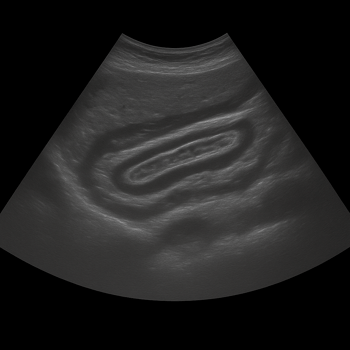

Imaging investigations

Abdominal ultrasound is a gentle examination that uses sound waves to assess organs such as the liver, gallbladder, kidneys, and ovaries. It is particularly useful for detecting gallstones, cysts, or fluid in the abdomen, but it does not show details from inside the intestines. An magnetic resonance imaging (MRI) of the abdomen provides more detailed images of soft tissues and may be used when there is suspicion of inflammatory bowel disease or a tumor. In typical IBS cases without warning signs, it is rarely needed.

Ultrasound Abdominal

• Ultrasound of the abdomen shows the liver, gallbladder, pancreas, kidneys and other abdominal organs in real time.

• Recommended for abdominal pain, swelling, nausea or elevated liver values.

• Quick, painless and radiation-free examination of the internal organs of the abdomen.

• Written opinion and recommendation from a specialist doctor are included.